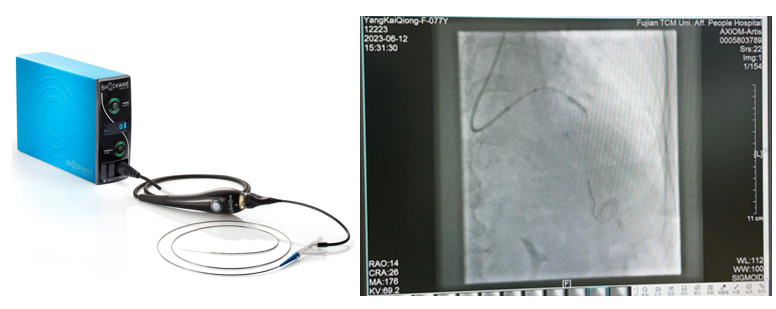

冠脉内冲击波治疗术